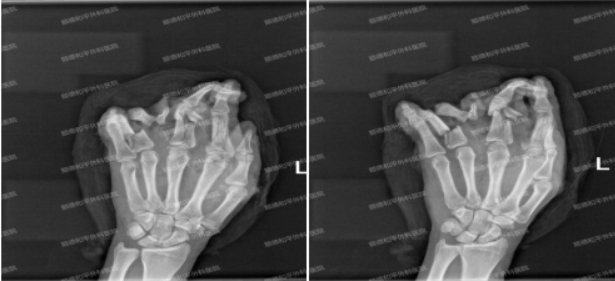

拍片检查示:左手第2掌骨远端及第3掌骨中远段、示指近中节指骨、中指近节指骨、环指近节指骨骨折,环指指间关节脱位。

2小时后患者入院,收入我院手显微外科三区进一步治疗,手三区医生团队第一时间对患者进行仔细检查。判定是一个严重的手掌手指毁损伤,同时伴有大量肌腱、血管、神经、指骨断裂错位。需要行急诊手术进行探查修复,对部位复位内外固定,再对肌腱、血管、神经进行吻合修复。

术式:左手清创,骨折复位内外固定,血管,神经,肌腱,甲床修复术,静脉皮瓣移植,供区VSD吸引术。